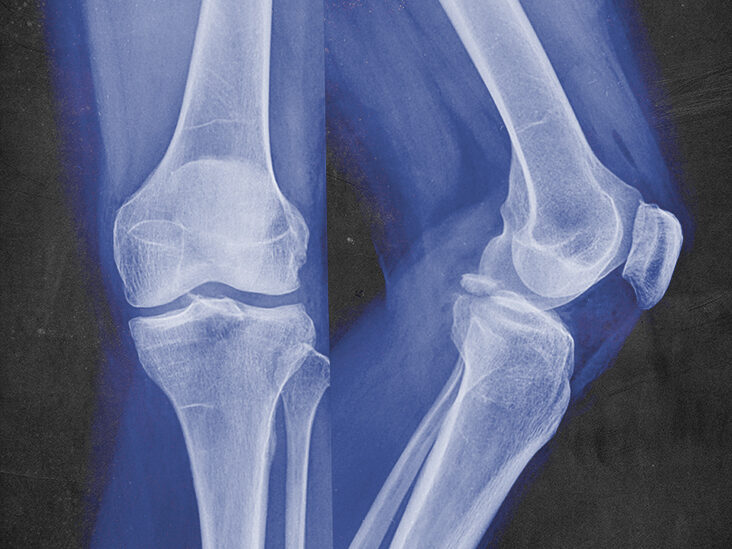

Fractures, also known as bone fractures or broken bones, are typically caused by injuries, accidents, or falls. The fractures can take place along the length of a bone or straight across the bone. The break in the bone can change its shape, split it in two or leave it in many pieces. Fractures usually take time to heal.

Fractures often occur due to injuries and accidents when a bone runs into a powerful force that it cannot withstand. Another reason for fracture can include ageing. As a person ages, their bones weaken, a condition also known as osteoporosis.